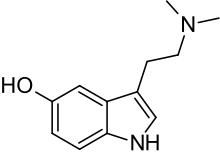

| Bufotenin | Animals, plants, fungi | 5-OH | CH3 | CH3 | 5-hydroxy-N,N-dimethyltryptamine | 487-93-4 |